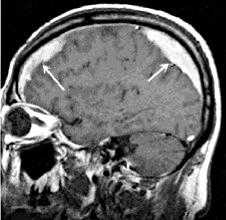

Решающими методами в диагностике субдуральной гематомы являются КТ и МРТ головного мозга. В диагностике острых гематом предпочтение отдается КТ головного мозга, которая в таких случаях выявляет однородную зону повышенной плотности, имеющую серповидную форму. С течением времени происходит разуплотнение гематомы и распад кровяных пигментов, в связи с чем через 1-6 нед. она перестает отличается по плотности от окружающих тканей. В подобной ситуации диагноз основывается на смещении латеральный отделов мозга в медиальном направлении и признаках сдавления бокового желудочка.

При проведении МРТ может наблюдаться пониженная контрастность зоны острой гематомы; хронические субдуральные гематомы, как правило, отличаются гиперинтенсивностью в Т2 режиме. В затруднительных случаях помогает МРТ с контрастированием. Интенсивное накопление контраста капсулой гематомы позволяет дифференцировать ее от арахноидальной кисты или субдуральной гигромы.

МРТ ГМ. Сдавление височной доли (зеленая стрелка) головного мозга объемным образованием (красная стрелка)